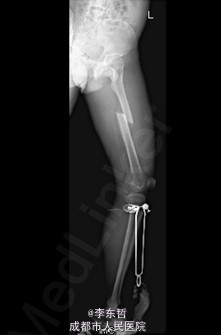

初步诊断:1、左股骨中段横行骨折,2、右小腿皮肤软组织裂伤清创缝合术后。 诊疗计划:1、向患者及家属交待病情及注意事项。2、向上级医生汇报患者病情。3、完善术前相关检查。4、给予皮肤牵引、抬高患肢等对症处理。5、拟进一步手术治疗。6、密切观察病情变化,根据病情及时处理

随访无特殊